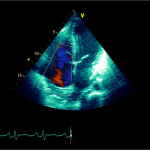

Ecocardiografia transtoracică

- Formaţiune hiperecogenă cu suprafaţa neregulată, care tapetează peretele liber al VD, grosime de 12 mm

- Dispusă de sub planul valvei tricuspide până in apropierea conului de ejecţie al valvei pulmonare

- SIV aplatizat

Ecografia transesofagiană:

Confirmă datele de la ecografia transtoracică